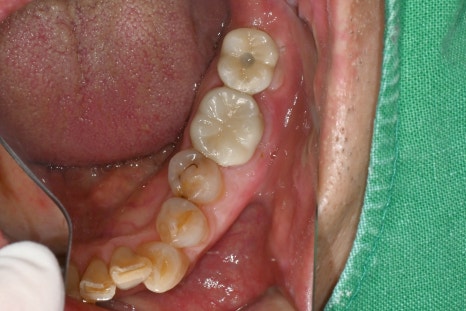

📸 환자 치료 전·후 사진

왼쪽 사진: 임플란트에 메웠던 레진이 떨어져 구멍이 그대로 드러난 모습입니다. 음식물 끼임의 위험이 있어 빠른 치료가 필요했습니다.

오른쪽 사진: 탈락된 부분에 레진을 다시 채워 깔끔하게 마무리한 모습입니다.

자연치아와 조화롭게 복구되었고, 통증이나 불편함 없이 사용 가능합니다.